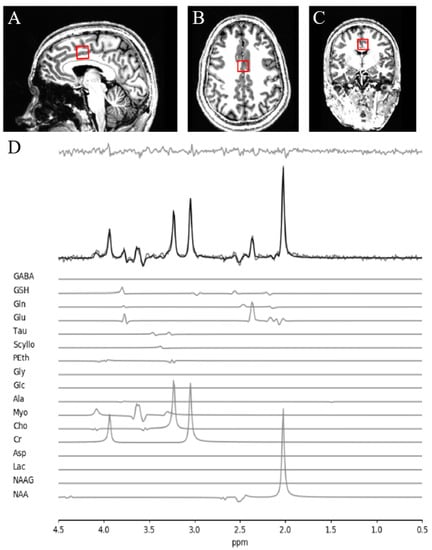

2.2. MRS Acquisition and Analysis